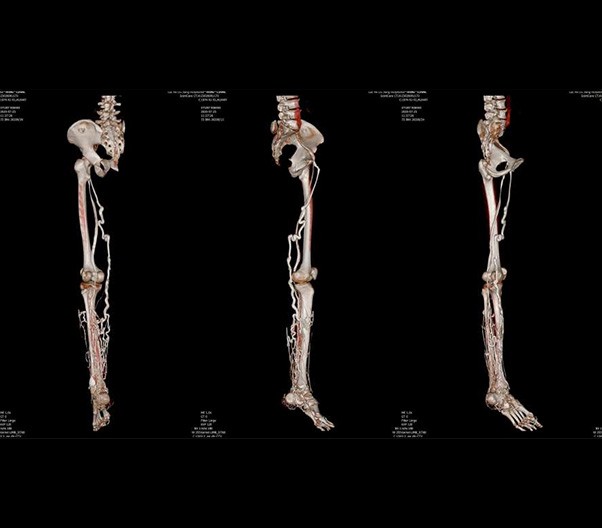

Intelligent digital tilt head AI positioning

Auto positioning and imA technology are enabled by the Polaris navigation system